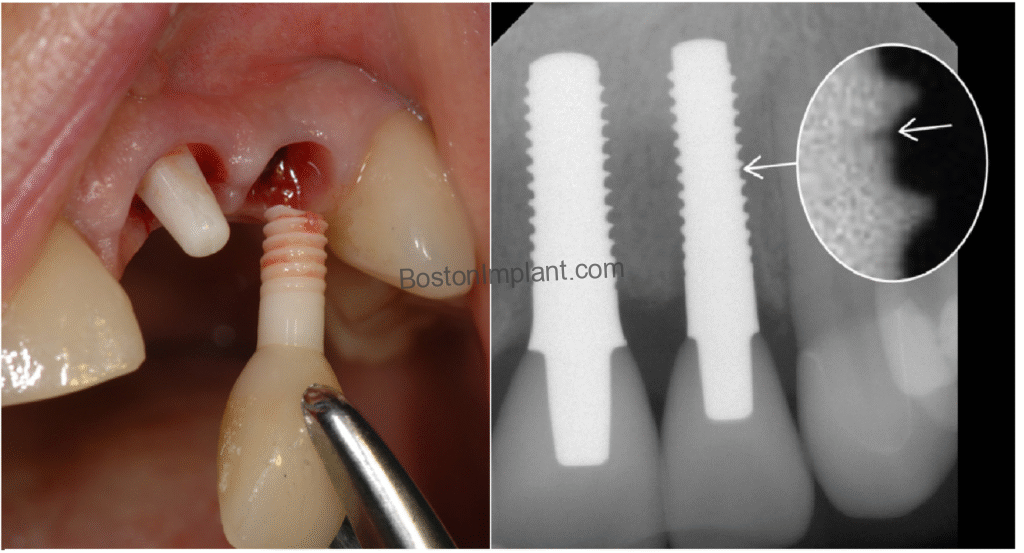

Fortunately, there is a hybrid approach that provides the strength of titanium and the aesthetics of ceramic:

- The Implant: We place a standard, durable titanium-alloy implant in the bone, where its strength and resilience are needed most.

- The Abutment: We use a white ceramic abutment (the piece that connects the implant to the crown).

With this hybrid approach, the portion of the restoration visible near the gumline remains pure white, providing a beautiful, natural-looking result. You receive the proven long-term durability of titanium, securely positioned below the bone, combined with the aesthetic advantages of ceramic exactly where it’s seen.